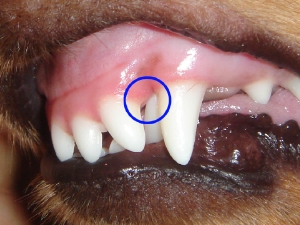

まずは全身麻酔にて乳歯犬歯を抜歯します。

実際移動を予定している犬歯の位置は青い歯で示した場所です。犬歯を矢印で示すように移動させます。